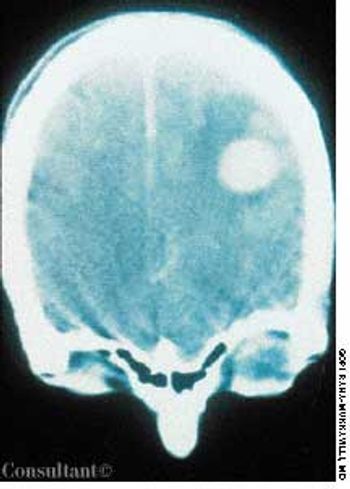

A 32-year-old man who had HIV disease complained of headache, fever, and weakness on his right side. His history included intravenous drug use, Pneumocystis carinii pneumonia, and mucocutaneous candidiasis.